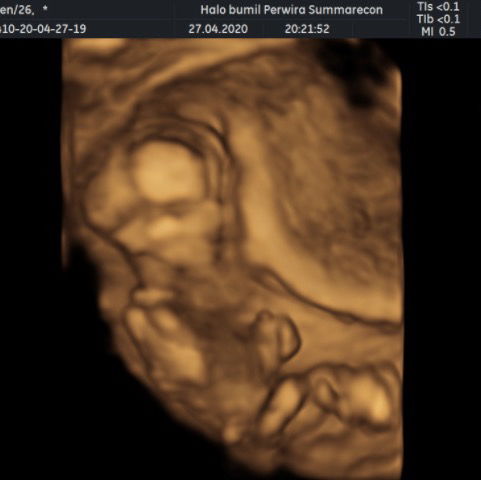

Usg 4d debayku

Assalamu’alaikum bunda Ini hasil 4d aku, yg kemarin terupload yg 2d sekarang 4d nya ? Alhamdulillah dedenya sehat dan aktif banget usianya minggu ini 15 weeks ?? oh iya dedenya pas di usg sedang menghadap ke punggungnya bunda loh dia malu sm dokter ?